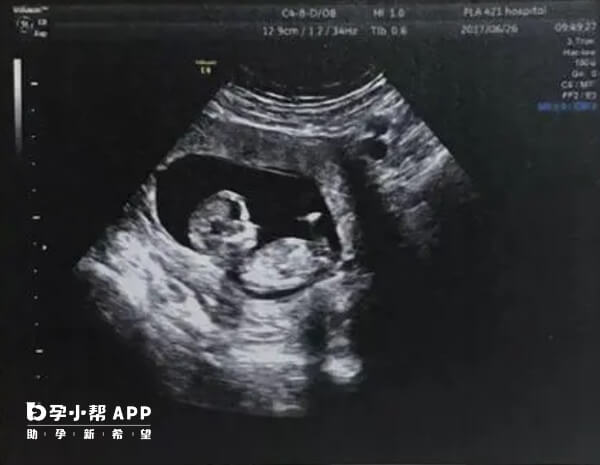

双胞胎小排畸是孕晚期的一项重要超声检查,主要用于评估胎儿在孕晚期的发育情况,排查可能存在的迟发性畸形,并为分娩提供重要参考。如果大家想要了解,双胞胎小排畸检查时间是什么时候,如下所示:

孕28-32周阶段胎儿器官发育基本完善,羊水量适中,便于观察双胎结构及排除迟发性畸形〈(如脑积水、肠道闭锁等)。这时进行双胞胎小排畸,可评估胎儿生长趋势、胎盘功能及羊水分布,尤其对双胎输血综合征等并发症的筛查至关重要。

重点检查脑部(如脑积水、小头畸形)、心脏、腹部脏器(如肾脏、肠道)、脊柱和四肢等,排查孕中期未发现的迟发性畸形,如部分泌尿系统畸形、肠道闭锁等。

测量胎儿双顶径、股骨长、腹围等指标,评估胎儿大小是否与孕周相符,判断是否存在生长受限或过大情况。

观察胎盘位置、成熟度,羊水量是否正常,以及脐带是否存在绕颈、打结等异常。